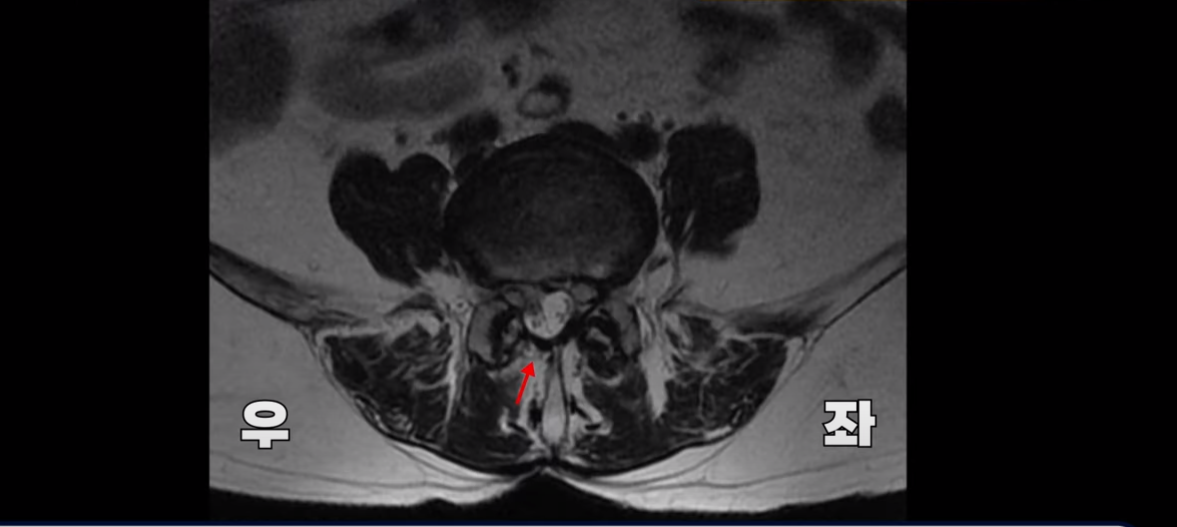

이 환자분 MRI를 보면 보시다시피 4번, 5번 디스크 파열로 오른쪽으로 심하게 밀려 나와있습니다.

그래서 이분은 오른쪽 엉덩이와 오른쪽 다리에 심한 방사통이 있으셨습니다.

여기 보시다시피 과거에 수술 받은 결과로 뒤쪽의 후관절 뼈 일부가 없어진 것이 보입니다.